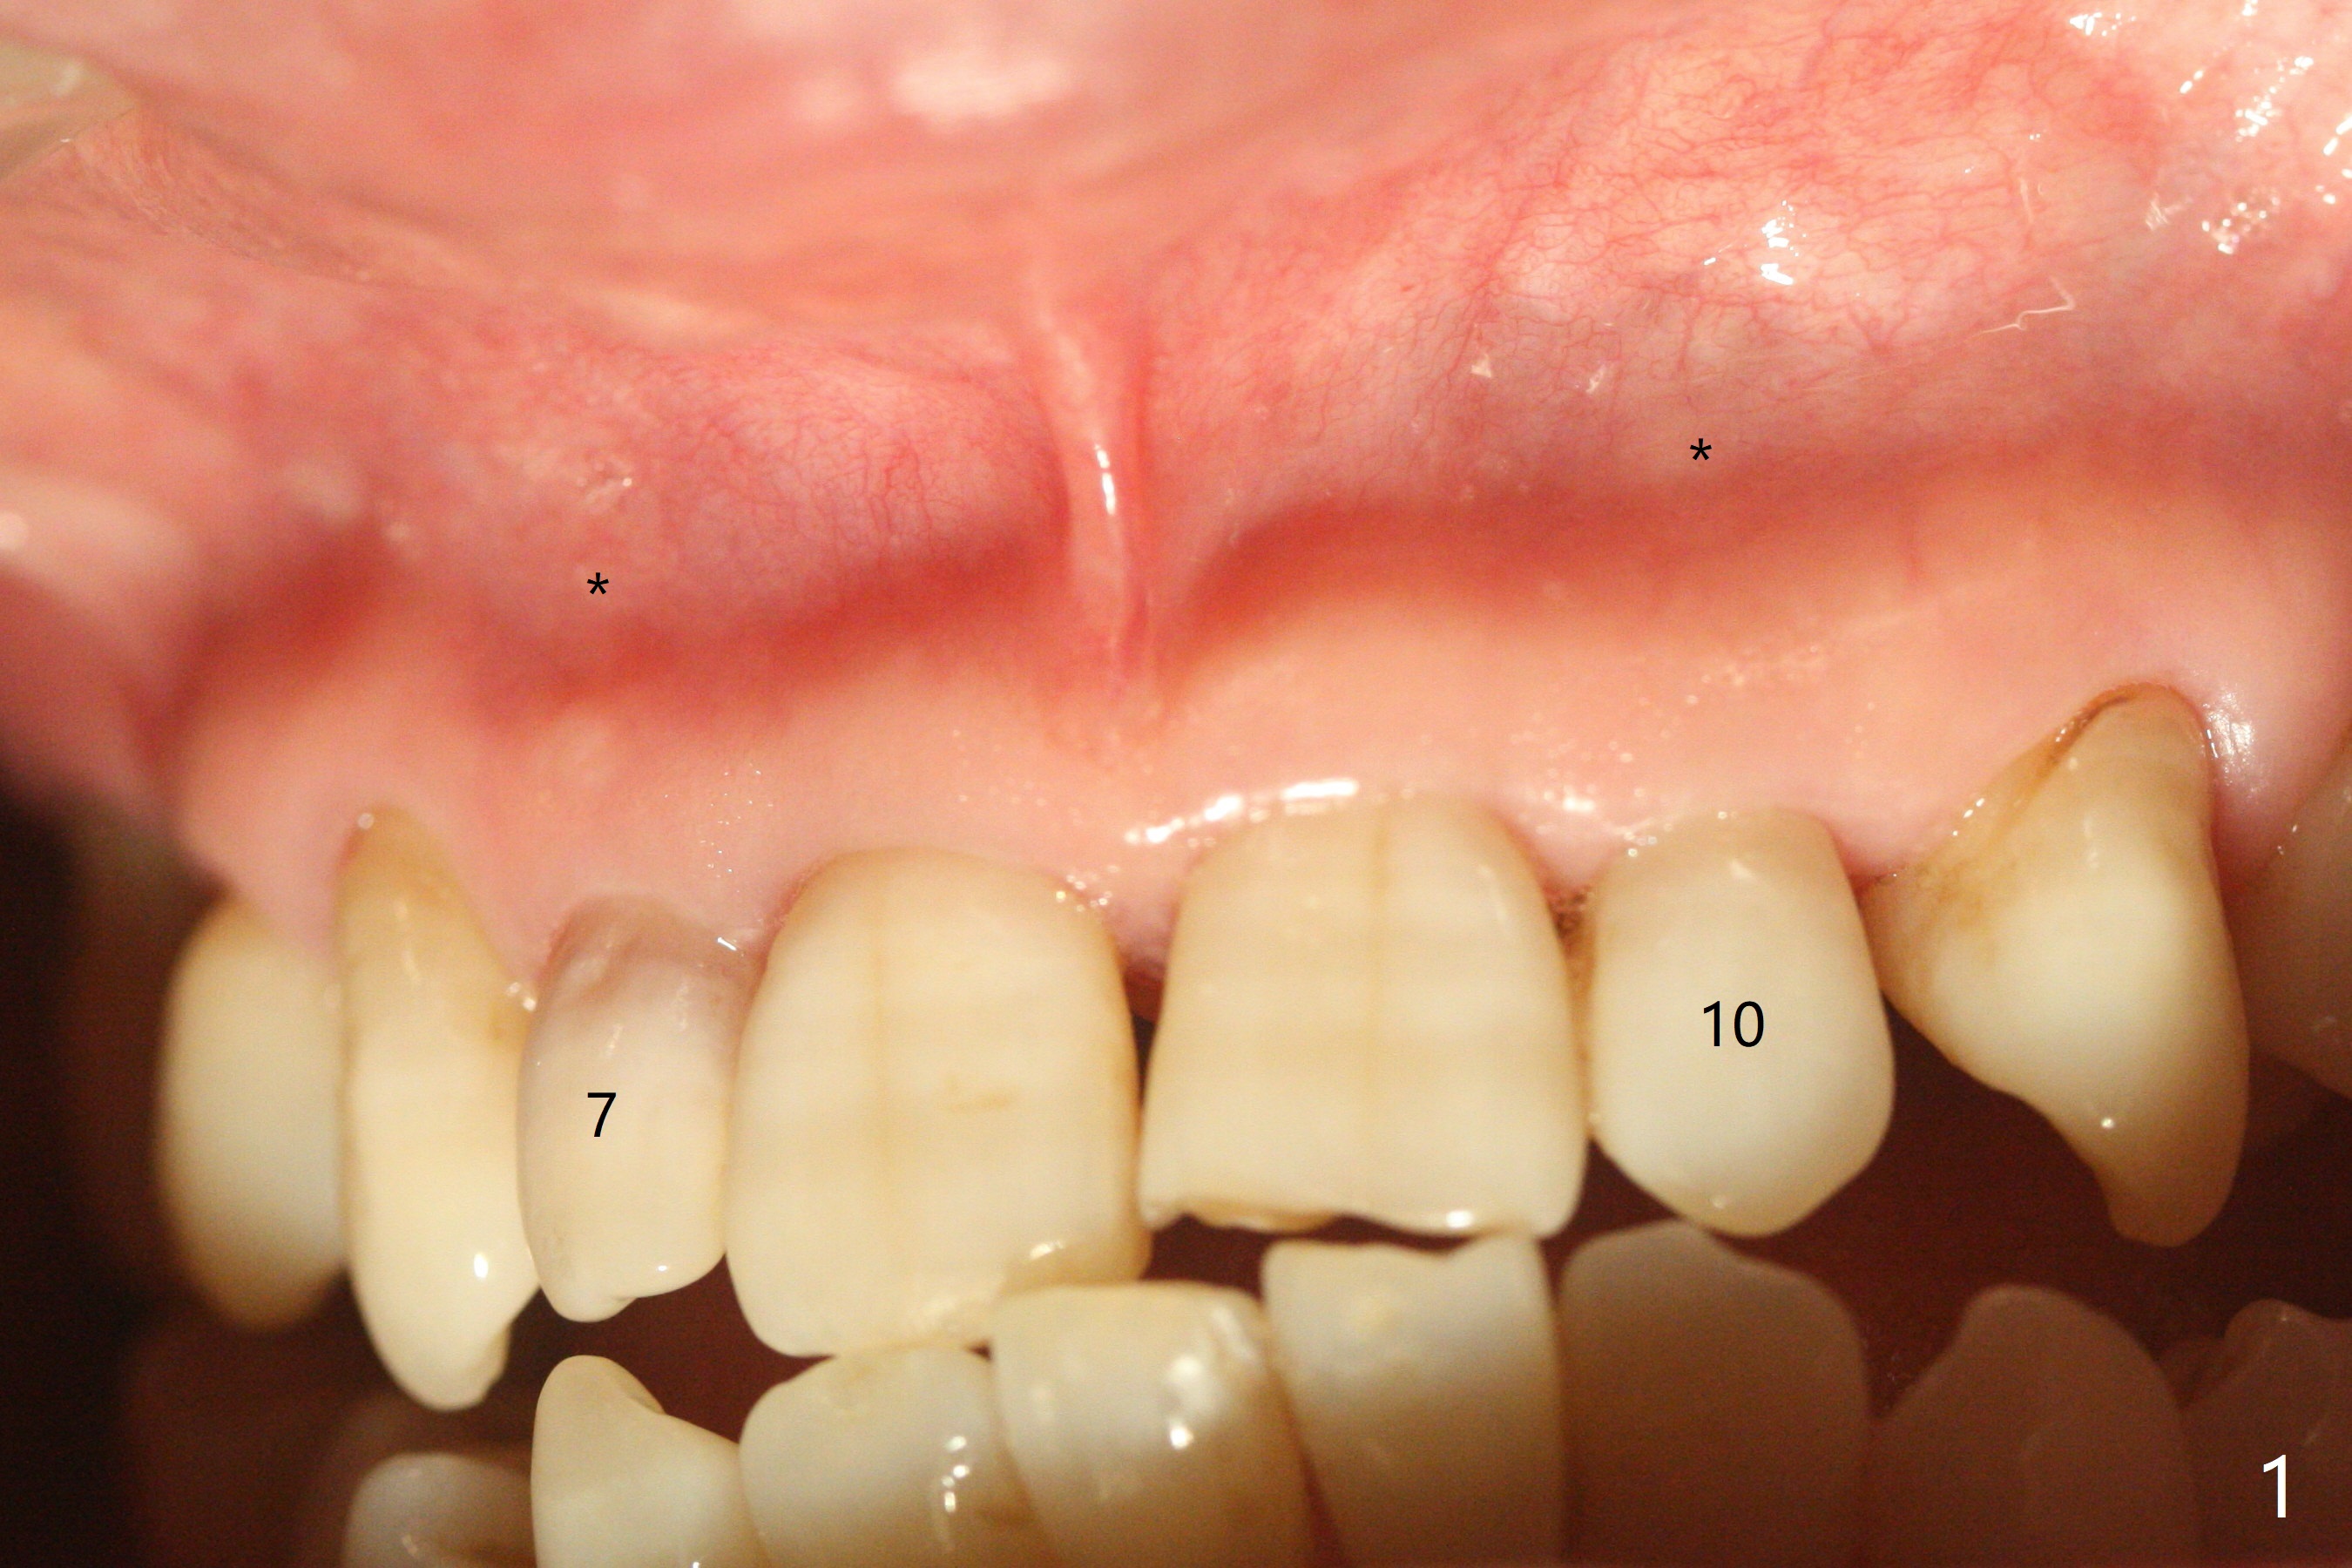

A 45-year-old woman presented to office for new patient examination. The latter reveals discoloration (Fig.1 necrosis on pulpal test; * labial concavity), microdontia with possible root canal malformation (Fig.2: M) and large inverted pear-shaped cyst (Fig.3) of the tooth #7. Guarded prognosis will be emphasized prior to treatment.